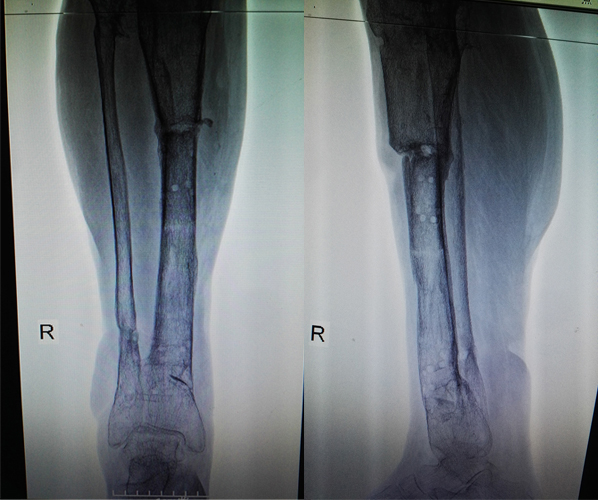

術(shù)后

愈合后